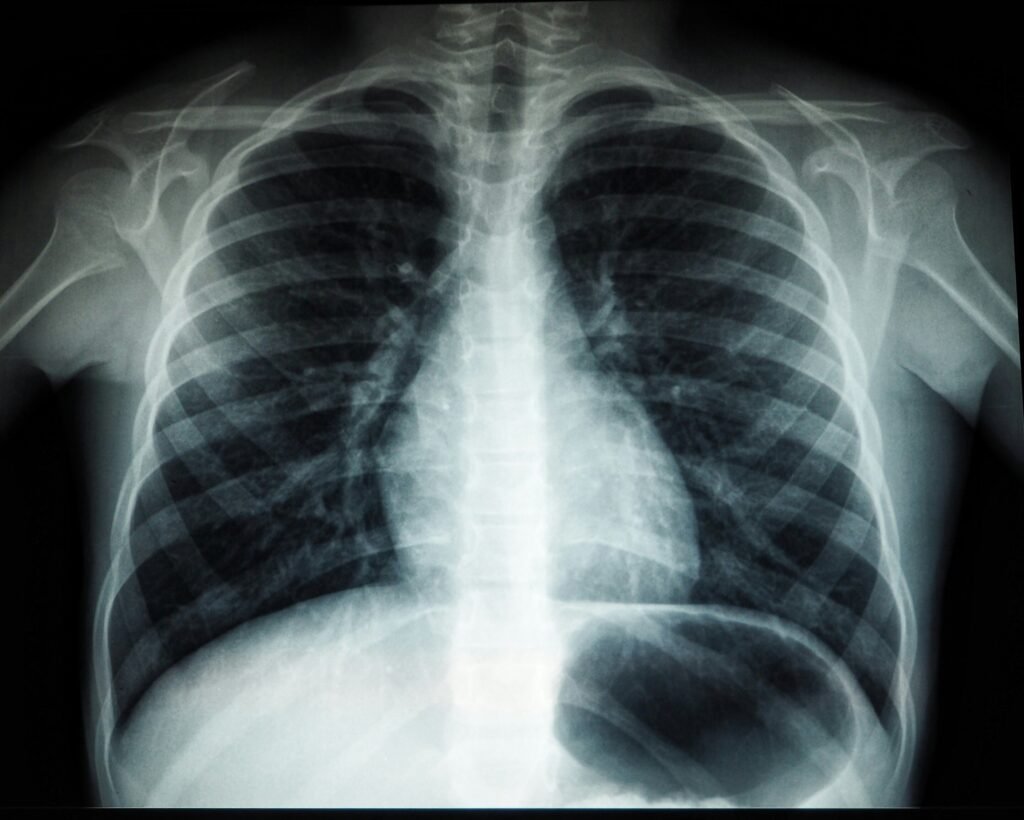

Lung cancer is the leading cause of cancer-related death in the country, yet only about 20% of eligible individuals undergo recommended screening. Early detection through screening can reduce the risk of lung cancer death, according to the National Cancer Institute. However, barriers such as identifying screening-eligible patients, limited awareness of screening recommendations, and time constraints during primary care visits hinder the screening process.

Key findings from the study include a 25% completion rate for screening CT scans among participants using the digital program, compared to 17% in the control group. Screening rates improved across all demographic and socioeconomic groups, with no reported complications from screening-related procedures.